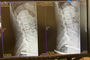

Am Montag begab Hans sich ins Krankenhaus, wo er mit einer CRT und diversen anderen Methoden auf mögliche Verletzungen nach dem Sturz untersucht wird. Endgültige Befunde liegen noch nicht vor. Aus dem Krankenhaus gab er eine leichte Entwarnung: «Die Ärzte haben nichts über irgendwelche Brüche gesagt, aber ich muss noch hierbleiben.»

Zu dem Sturz berichtete er: «Der Einschlag war sehr stark. Mein Helm wurde dabei zerstört. Die Bahnabgrenzung in Heerenveen ist lebensgefährlich. Schon 2019, als ich den Halswirbelbruch hatte, habe ich gesagt, dass man da etwas tun muss.»